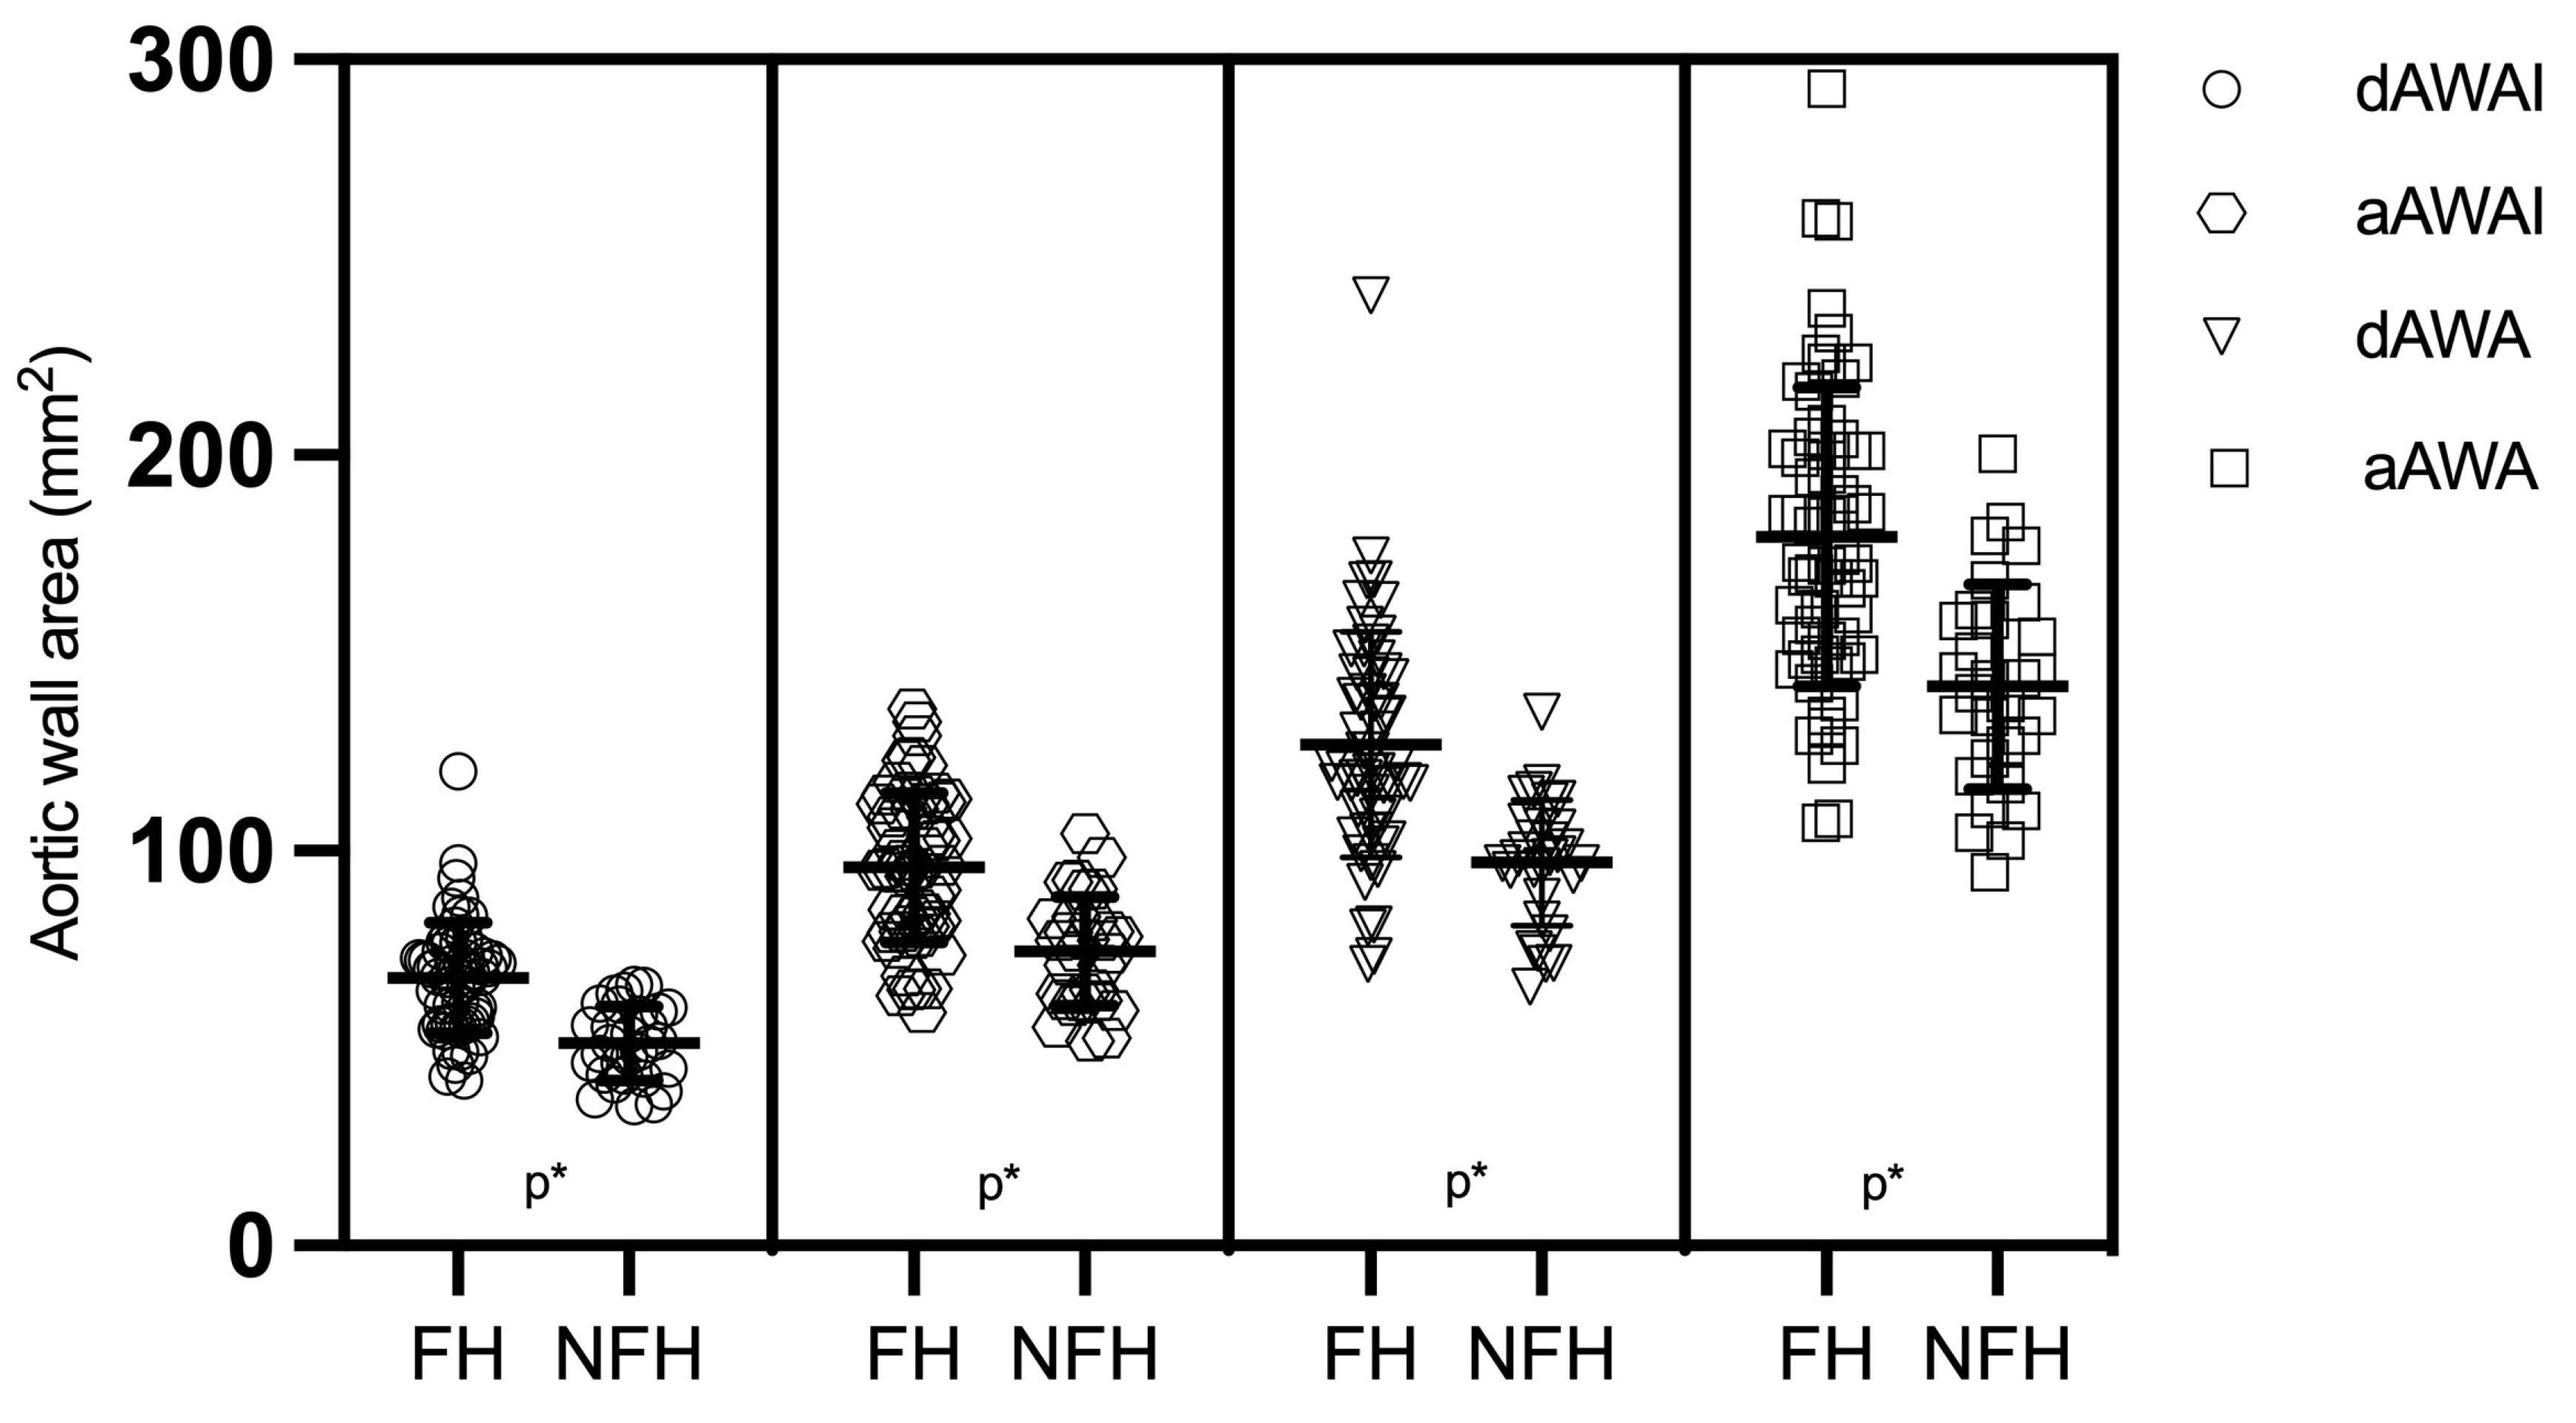

| aAWAI (mm2) | mean ± SD T2 | 95.7 ± 19.7 | 74.7 ± 13.5 | 0.001 |

| 97.6 | ||||

| dAWAI (mm2) | mean ± SD T2 | 67.8 ± 14.1 | 51.9 ± 9.8 | 0.001 |

| 68.2 | ||||

| dAWAI | 48.3 (29/60) | 6.7 (1/30) | <0.001 |

| aAWAI | 46.7 (28/60) | 6.7 (2/30) | <0.001 |